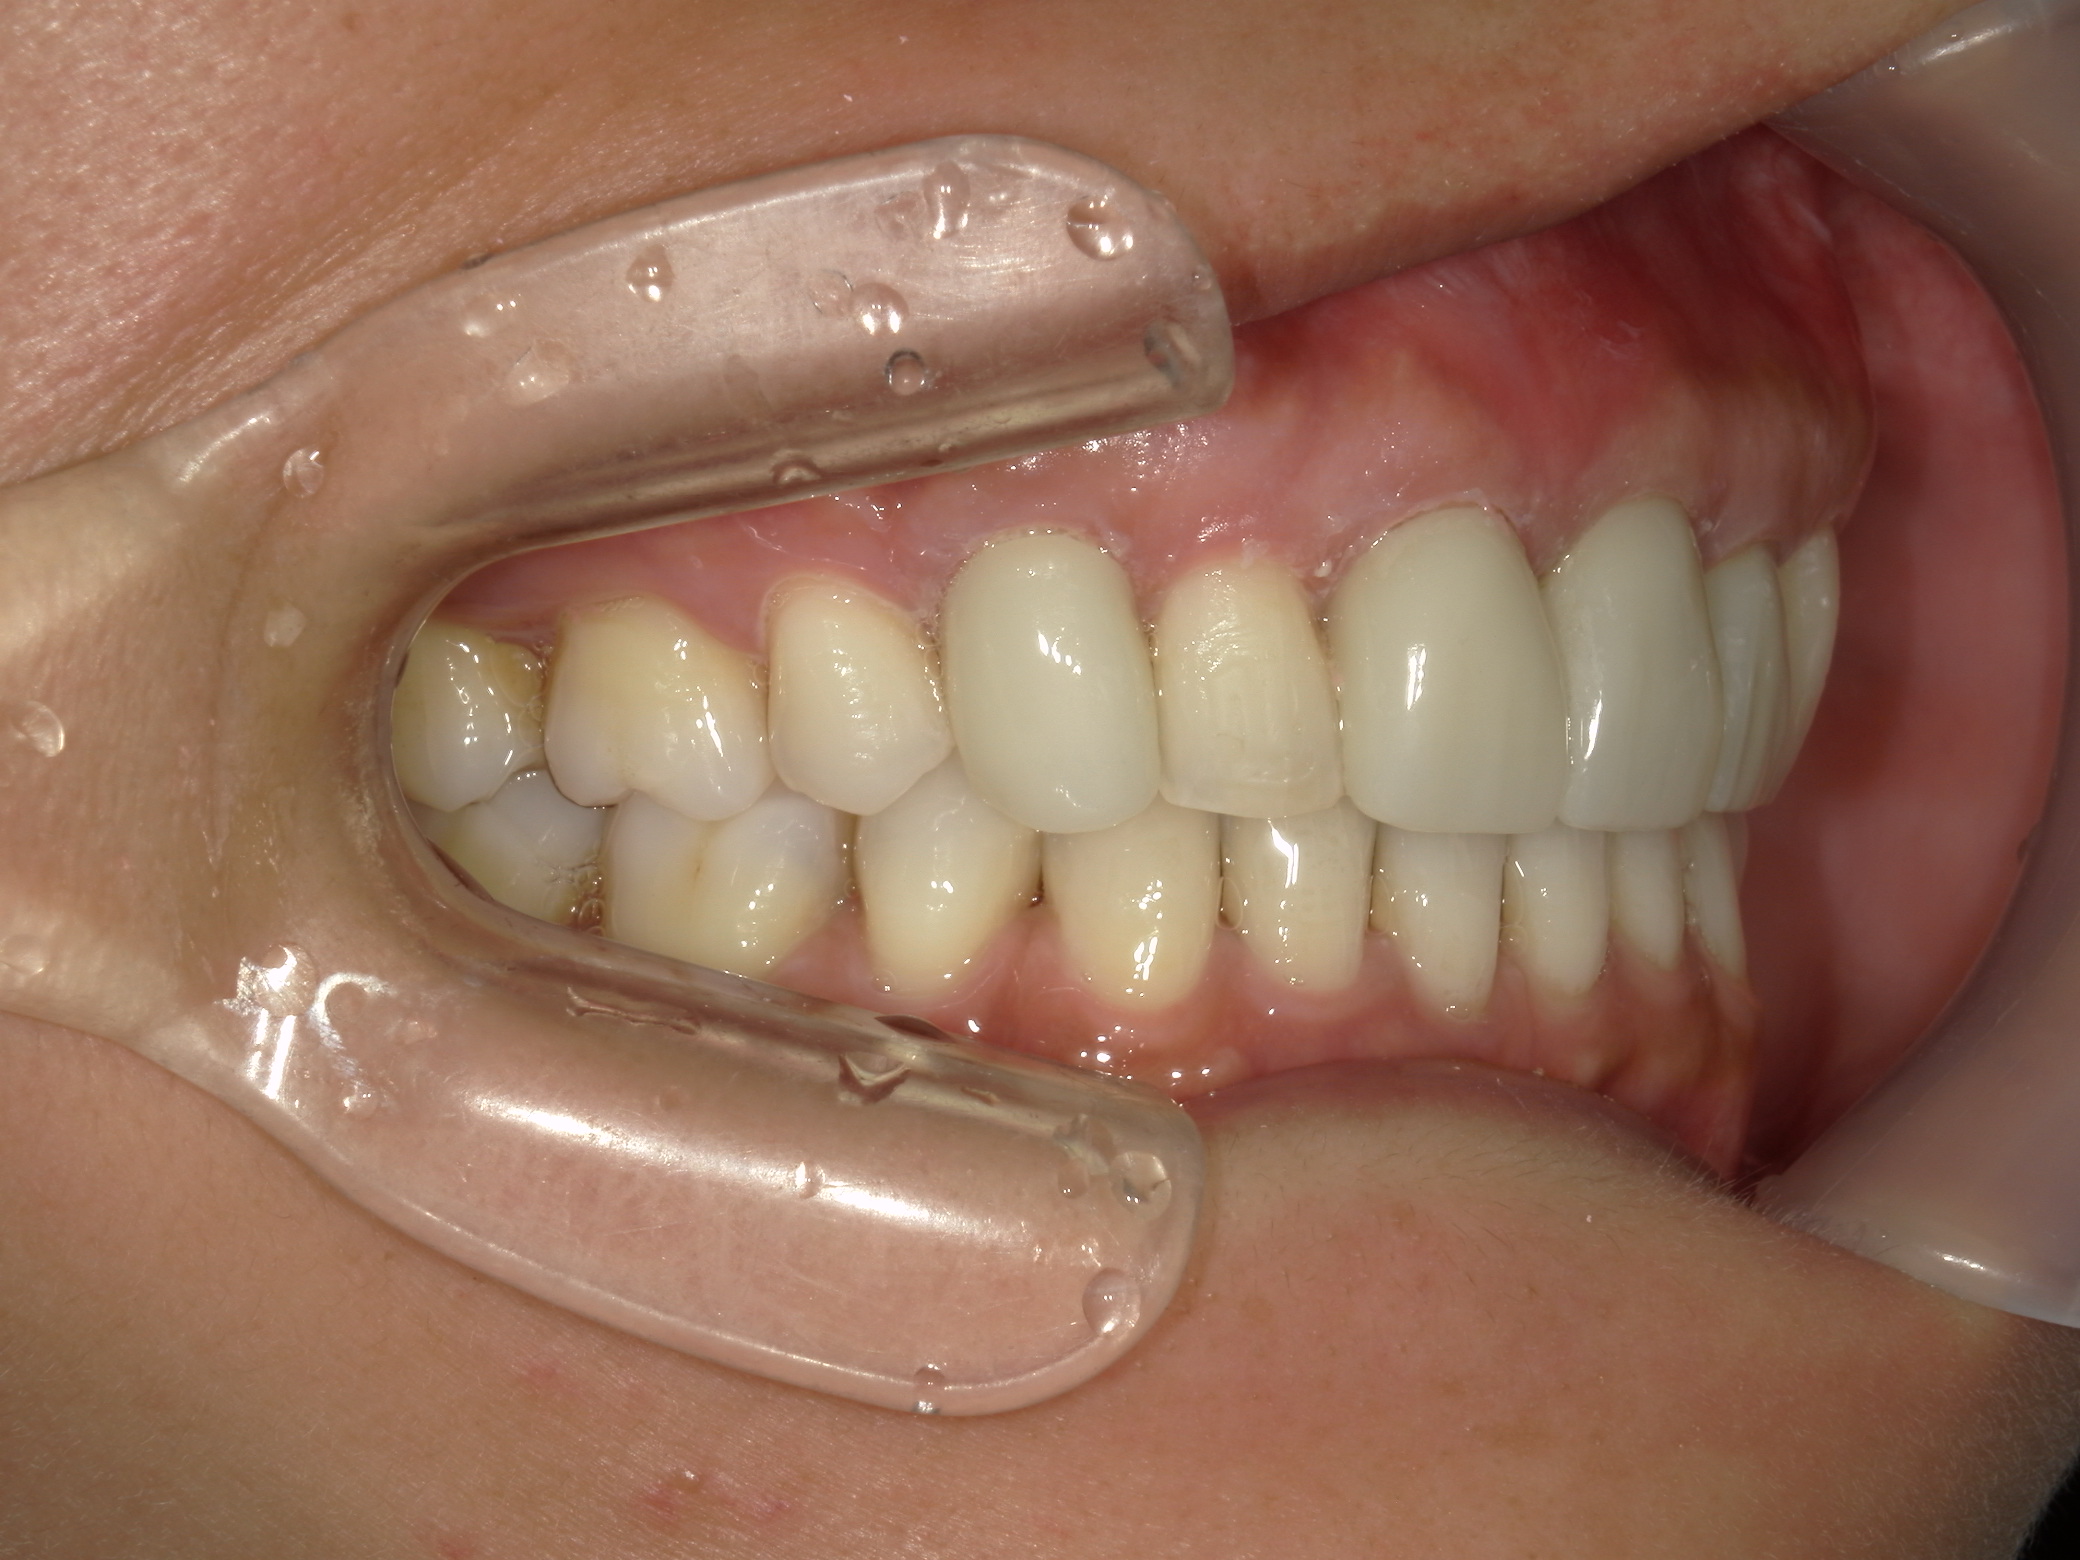

全顎ワイヤー矯正 症例(82)

主訴: 前歯の歯並びが気になる。

上下左右 第一小臼歯(4本)、左右上 親不知(2本)を抜歯。

ミニインプラント、アップライトスプリングを併用。

矯正前に左右上前歯4本を仮歯に変え、矯正治療後にセラミック(SHT)に冠せなおしました。

カテゴリー : ガタガタ(叢生)